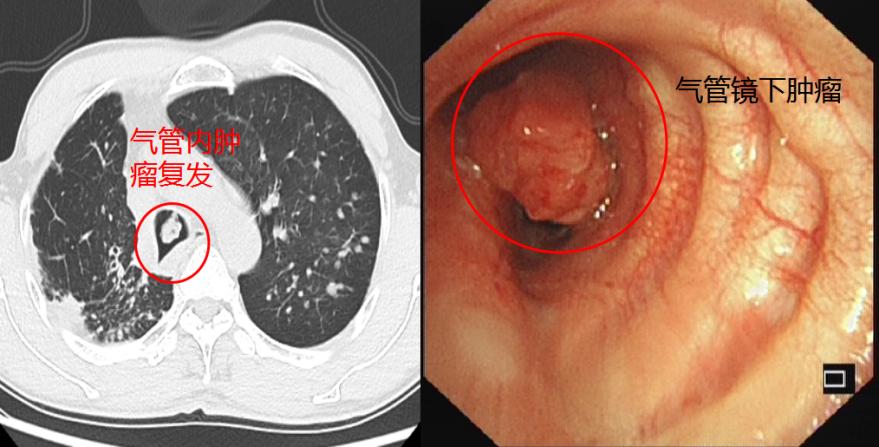

经过气管镜下治疗、手术及化疗后,李先生一直觉得很好,没有重视也没来复查。直到3年前再次出现气喘,他预感到不好,可能是肿瘤复发了,就赶紧来找我复查,结果肺部CT一查,果然是肿瘤复发。

因他不愿化疗,肺内有转移灶,没有手术机会,我们再次使用气管镜下氩等离子体凝固治疗(APC)切除肿瘤,并用CO2冷冻减缓肿瘤和肉芽生长。